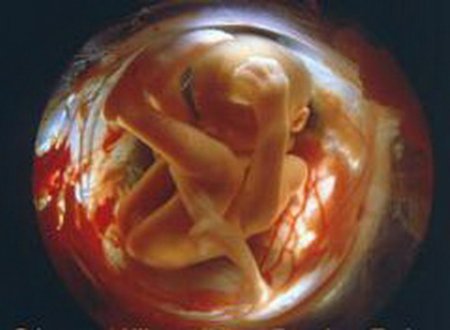

В этот период у плода появляется и начинает функционировать вестибулярный аппарат. Чем больше в этот период двигается мама, тем полезнее для малыша. Кожа малыша прозрачна, ручки растут быстрее, чем ножки. Выпрямляются голова и шея плода, уже сформировалось личико. Мышцы и кости проглядываются под кожей, не имеющей жирового слоя. У малыша хрящевой скелет, плод начинает активно шевелиться.

Прослушивается частое сердцебиение плода. На 10-й неделе можно уже различить пол ребенка. На 12-й неделе у малыша сближаются глаза, уменьшается рот, появляются голосовые связки, широко раздвинуты ноздри.

Над глазками и верхней губой появляются первые волосики. Ежедневно малыш растет на 1,8 мм и прибавляет в весе 1,4 гр. К концу 12-й недели длина ребенка составляет 8-9 см, а вес около 30 гр. Подробнее на видео.